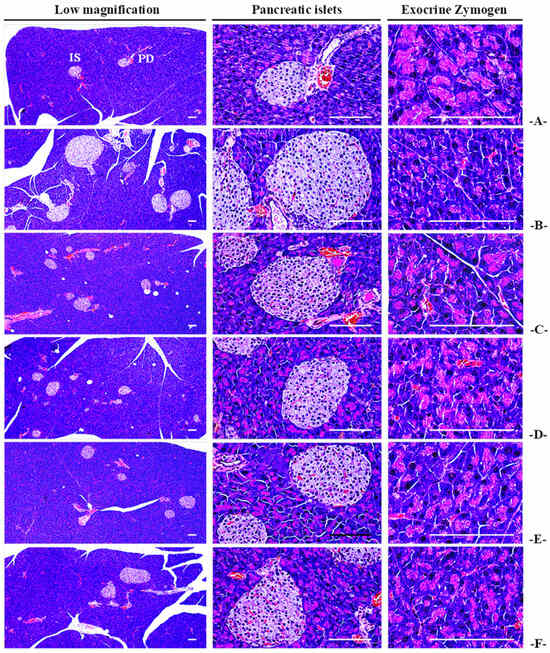

3.3.5. Histopathological Observations for Pancreatic Exocrine Zymogen Granules

3.4.3. Effects on the General Histopathology of Pancreatic Islands

3.4.4. Effects on the Immunohistochemistry of Pancreatic Islands